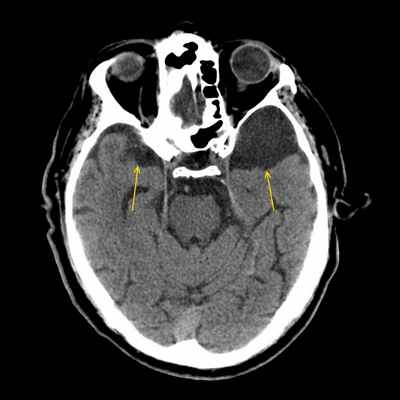

Компьютерная томография

Арахноидальные кисты четко отграниченные образования с невизуализируемыми стенками, вызывающие смещение прилежащих структур, при крупных размерах вызывающие ремоделирование костной костной ткани на данном уровне.

КТ-цистернография может помочь выявить связь субарахноидального пространства и кисты.Магнитно-резонансная томография

На изображениях они визуализируются в виде четко отграниченной полости с невидимыми стенками, оттесняющей прилегающие структуры, с сосдержимым характеризующимся паттерном аналогичным паттерну церебросиннальной жидкости (гиподенсивный при компьютерной томографии, гиперинтенсивный на Т2 взвешенных изображениях и гипоинтенсивный на Т1ВИ при магнитно-резонансной томографии). Они так же могу вызывать ремоделирование прилегающей кости.